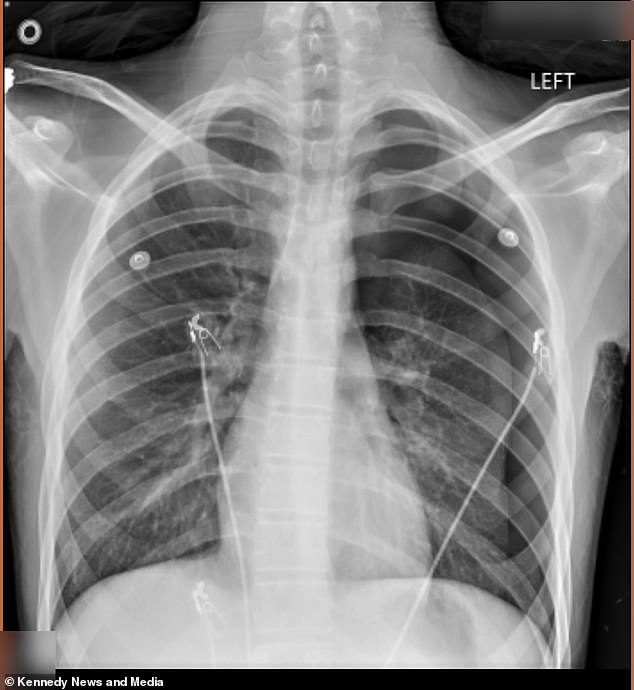

In September 2025, Dodge emerged from his school bus pale and in visible pain. His mother, recognizing the severity of his condition, rushed him to the emergency room. A chest x-ray revealed a shocking reality: 50% of his left lung had collapsed, a condition known as pneumothorax. This occurs when air escapes from the lung and accumulates in the chest cavity, creating pressure that can be fatal if not treated immediately. Doctors intervened by surgically inserting an 18-inch tube into his chest to remove the excess air and allow his lung to re-expand. Despite this intervention, Dodge continued vaping in secret, unaware of the damage he was inflicting on his body.

The situation worsened in January 2026 when Dodge called his mother, gasping for breath and in severe pain. This time, the medical team found his lung had collapsed again, necessitating a more invasive procedure called pleurodesis. During this surgery, doctors scraped the lining of his lung and stapled air-filled blisters, known as blebs, to the top of his lung. They then reattached the lung to the chest wall to prevent future collapses. The ordeal left Dodge physically and emotionally scarred. His mother described the experience as 'horrible,' questioning why her son had been chosen to endure such suffering. 'His friends tried [vaping] and then he tried it. I don't like it at all,' she said, her voice trembling with grief and frustration.